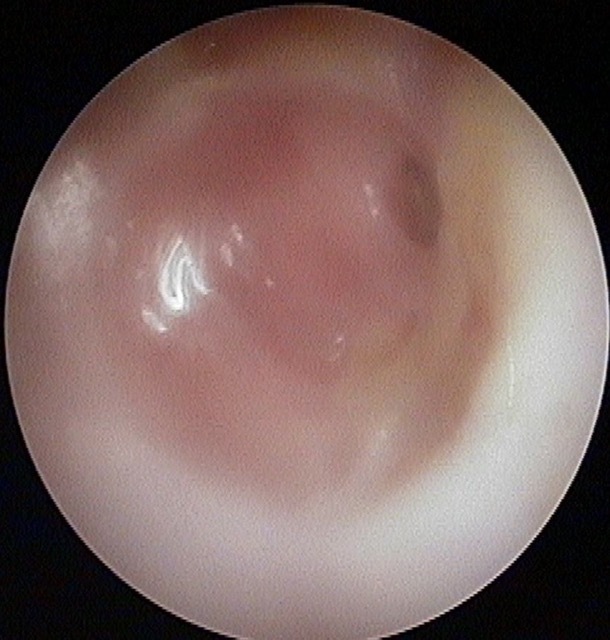

Perforation